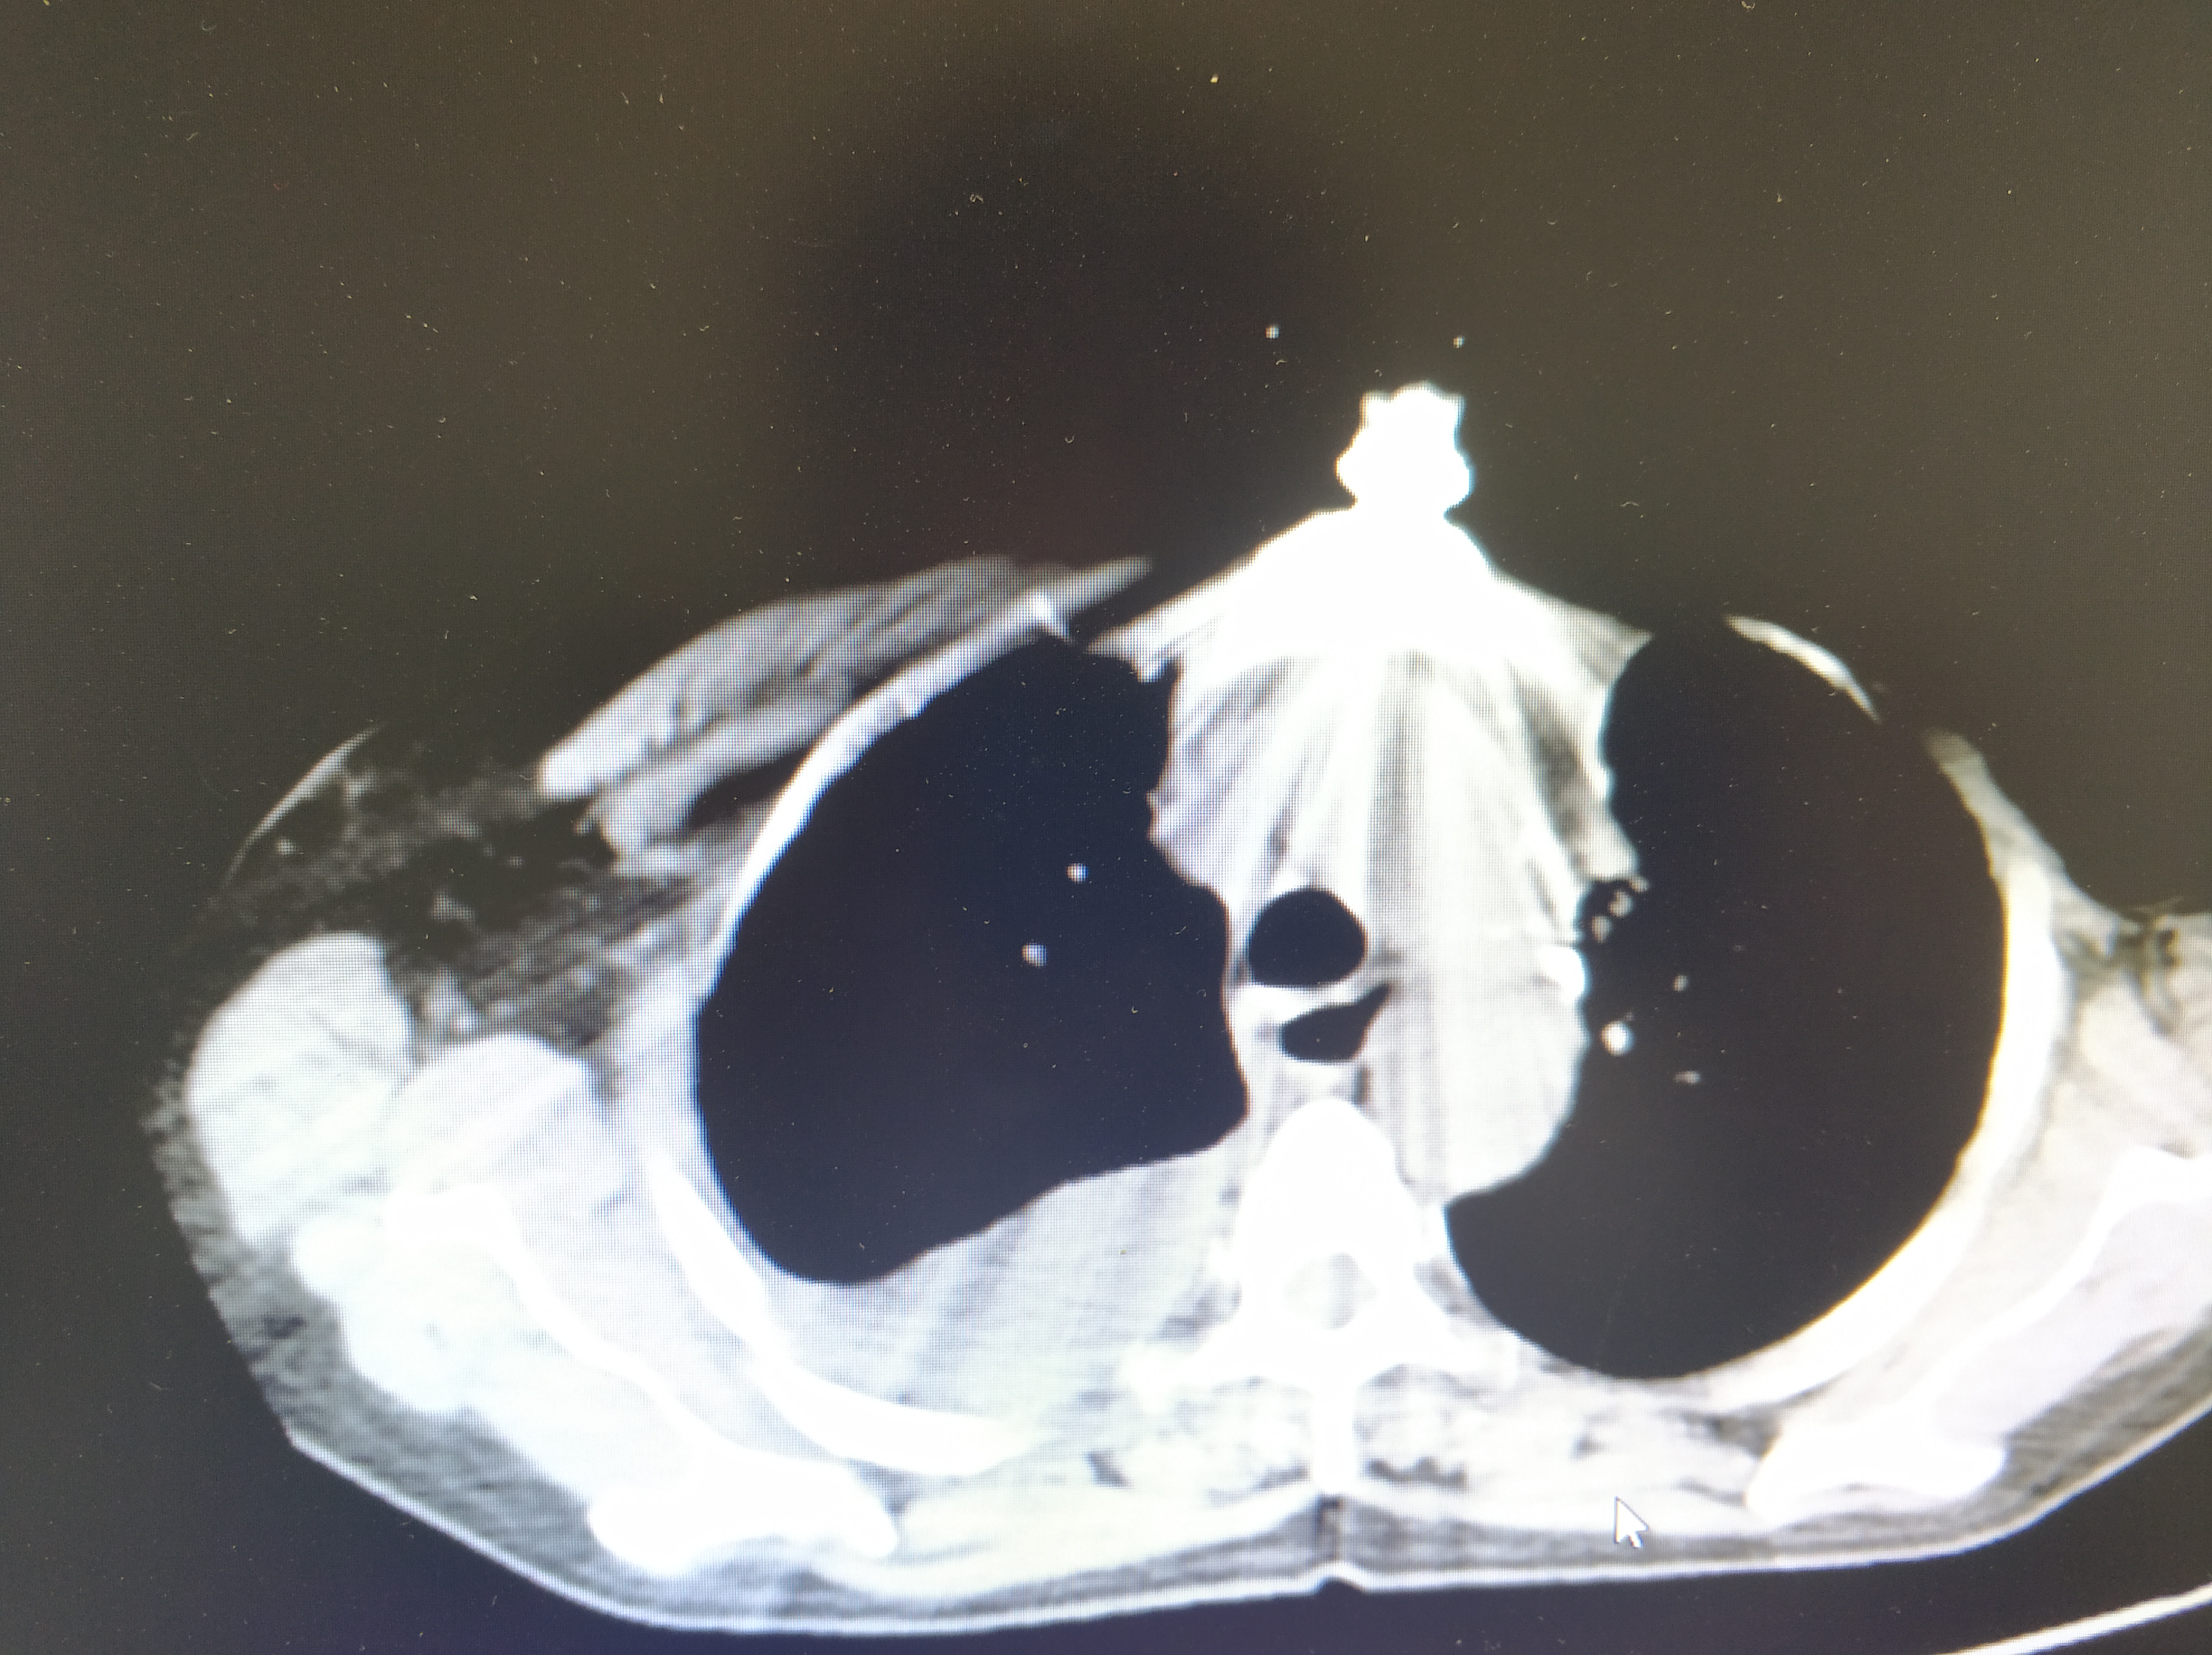

查出多发肺转移和双侧胸腔积液:这是一位67岁女性,3年轻查出乳腺癌,做

图片尺寸640x372